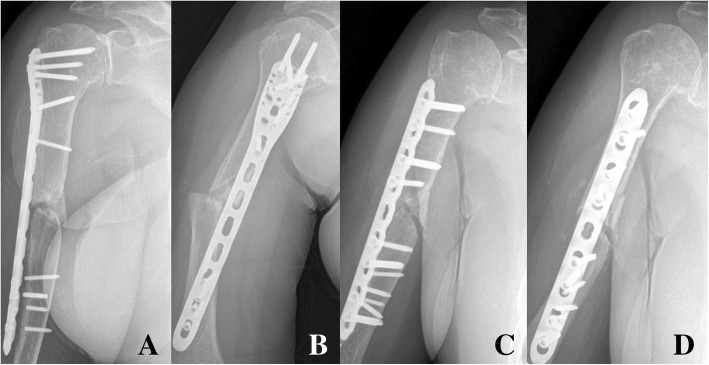

Fig. 4.

Anteroposterior and lateral X-ray showing the metal failure of spiral (Spiral wedge type, AO classification: B1) humerus shaft fracture of in a 74-year-old female patient (a, b). Using open approach, narrow locking compression plate was used with bone graft (c, d)